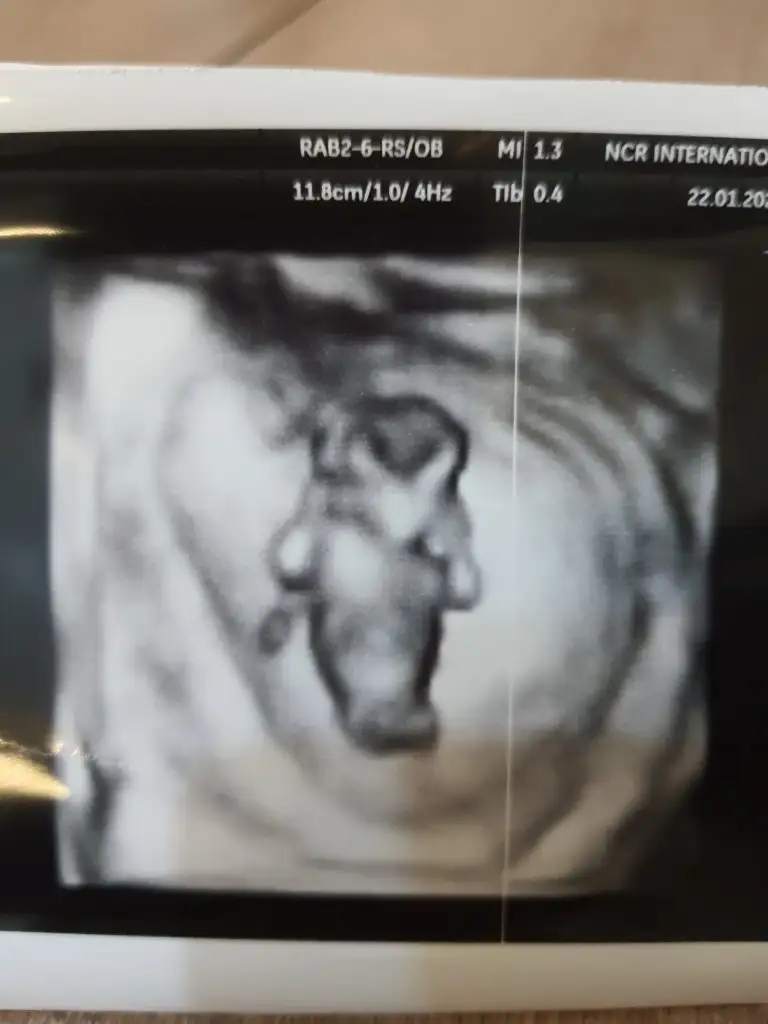

dr soylemeden siz gorun genital nub teorisi ( bebegin cinsiyeti)

Ben tahmin yürütüyorum... nub konusunda çok uzman değilim 🤷‍♀️ 2013 yılında ORKDM vardı bu postta o resmen nokta atışı yapıyordu nerdeyse tahminlerinde hiç yanılmıyordu öncelikle Allah sağlıklı uzun ömürlü hayırlı evlatlar versin....

13 hafta USG olursa paylaşın ilk bebekmi net usg olsa net tahmin ederim kesin kız yada erkek derdim canım